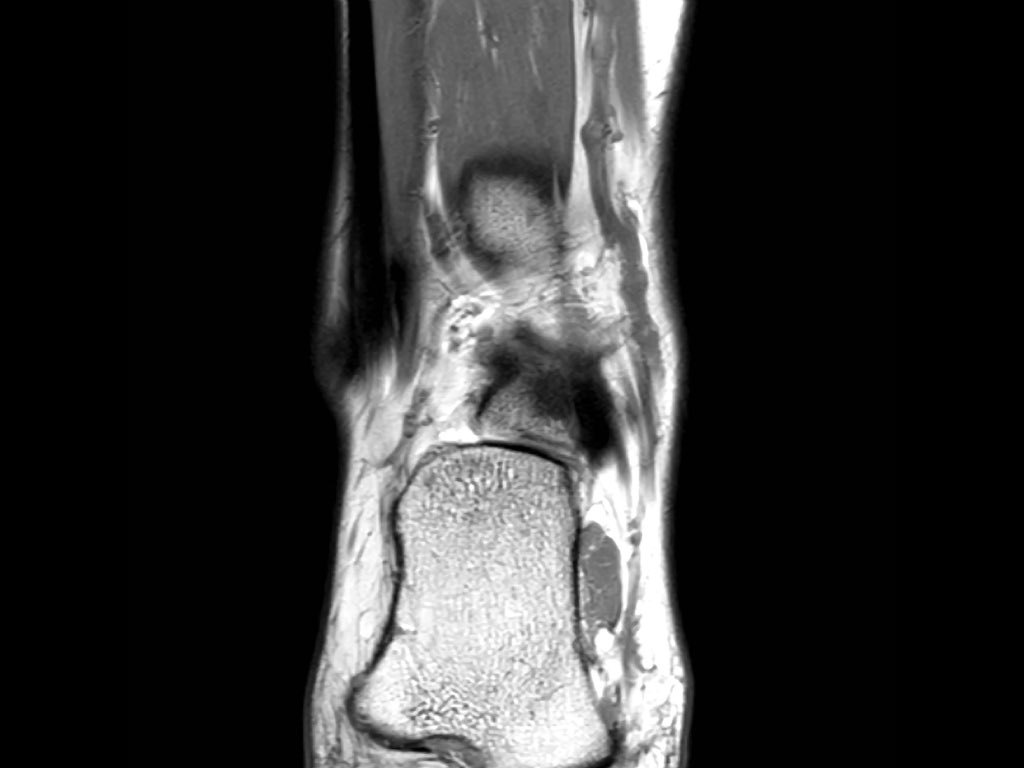

Cuộn qua các ảnh cắt vành.

Bạn có thể phóng to ảnh bằng cách nhấp vào.

Đây là hình ảnh của ba bệnh nhân có tổn thương dây chằng ATFL.

Bệnh nhân bên trái có phù nề nhẹ xung quanh dây chằng ATFL, trong khi bản thân dây chằng trông bình thường.

Đây có thể là căng dây chằng mức độ nhẹ (độ 1).

Thường được nhận thấy rõ nhất trên ảnh có kỹ thuật ức chế mỡ (fatsat).

Bệnh nhân ở giữa có dày lên và rối loạn cấu trúc, biểu hiện của rách một phần (độ 2).

Bệnh nhân bên phải có rách toàn bộ chiều dày (độ 3).